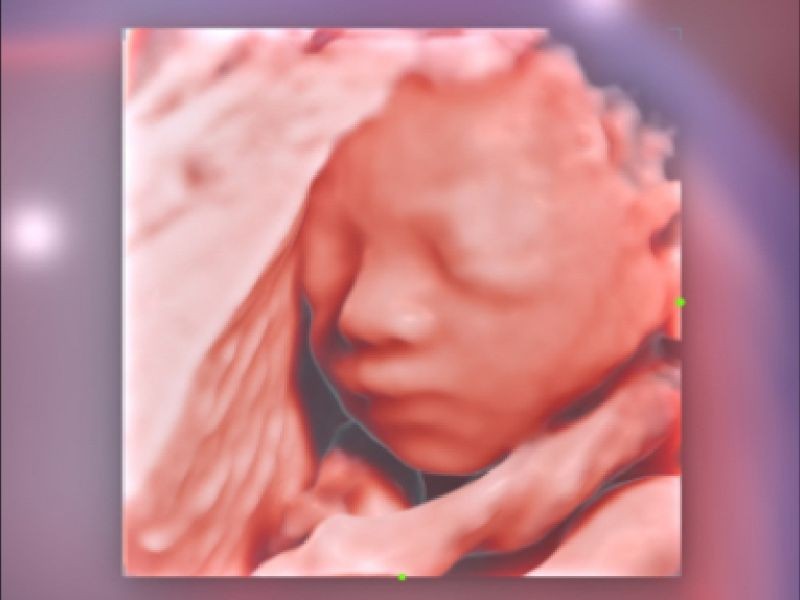

Realismo e clareza sem precedentes - iLive com Hyaline

Ao imitar múltiplas fontes de luz de intensidade variável, o iLive ajuda a melhorar significativamente a resolução anatômica detalhada tanto para estruturas superficiais quanto internas por meio de renderização de volume de alta velocidade.